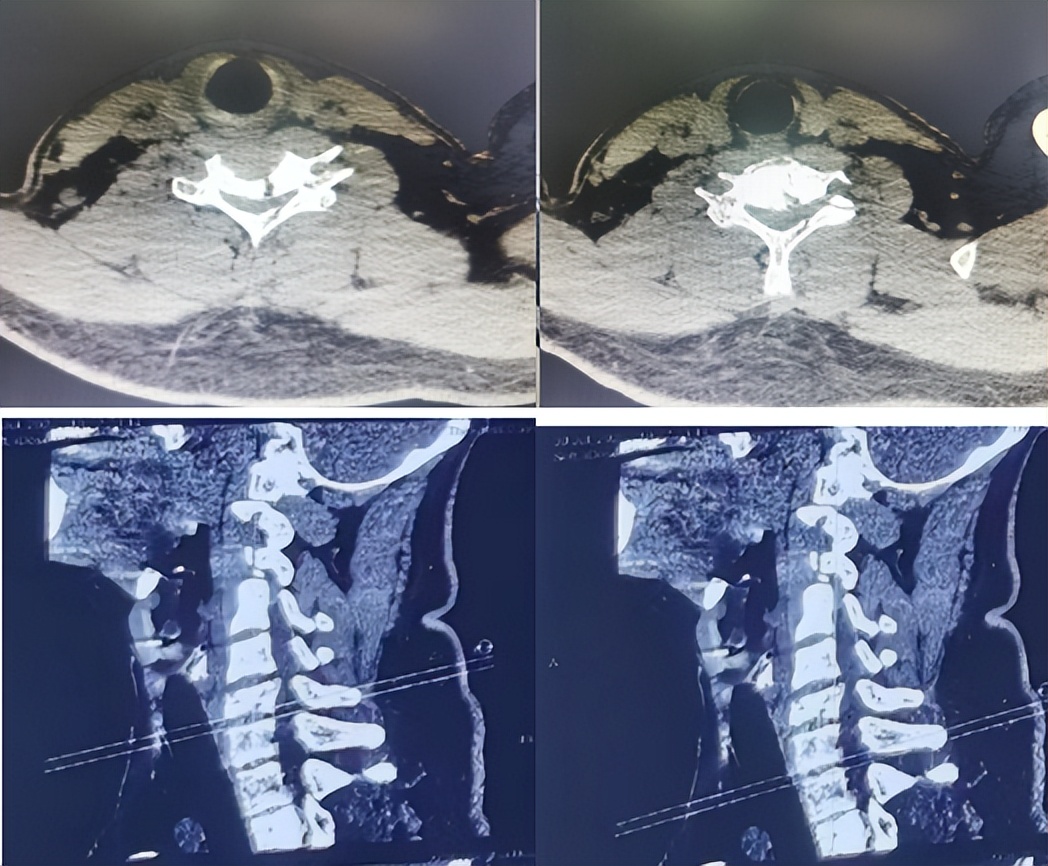

术前检查脊髓损伤平面

收入院后,急诊科医生查体发现,患者意识清楚,头顶部血肿,胸式呼吸消失,腹式呼吸存在,四肢及胸骨角平面以下躯干痛温觉、触觉均减退,会阴区感觉异常;上肢肌力2级,下肢肌力0级,大小便障碍。积极完善头部+颈椎三维CT及颈椎磁共振检查。